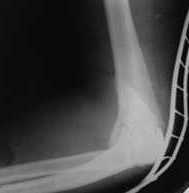

Уважаемые коллеги! Нужен Ваш совет, Подскажите пожалуйста, как можно в дальнейшем этому больному помочь. В марте первая операция, пришлось оперировать на 16 сутки в виду инфицированных садин и анемии. Заживление первичным натяжением,раняя разработка после операции, а через 2 нед болевой синдром,и постепенно движения в локтевом суставе ограничились до полного анкилоза. Повторно через 4 месяца вторая операция" артролиз,удаление оссификатов, удаление фиксаторов, реостеосинтез этой же реконструкционной пластиной и винтом" интраоперационно после удаления оссификатов и фиксаторов обнаружил, что перелом не сросшиеся, поэтому пришлось синтезировать заново. Зажило рана первично, объем движений в локтевом суставе сгибание 70, разгибание160, ротационные движения востановились полностью,вроде бы успокоились. Опять постепенно в течении 8 нед после повторной операции постепенно движения ограничились до 80 - 110, на снимке оссификат. Снимки во вложении, буду рад Вашим советам. Спасибо!С уважением Шухрат.